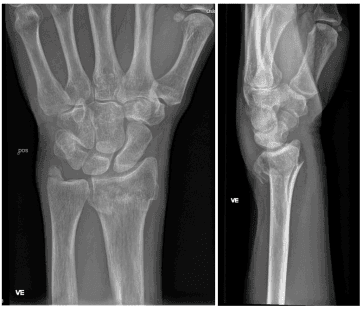

Røntgenbilder tatt forfra og fra siden bekrefter diagnosen (se over). Man ser etter feilstillinger, om det er brudd som innbefatter selve håndleddet, om det er ujevnheter i leddspalten, eller om det foreligger andre beinskader.